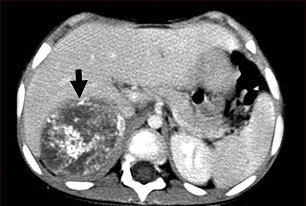

This CT scan of the upper abdomen shows a large tumor (neuroblastoma) on the person's right side (lower left side of picture). The tumor is behind the liver and is pushing the liver forward and may have possibly spread into the liver tissue.